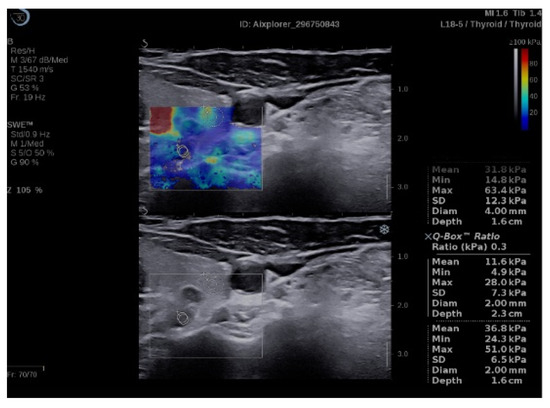

2.4. Elastography Exam

3.1. SWE Results